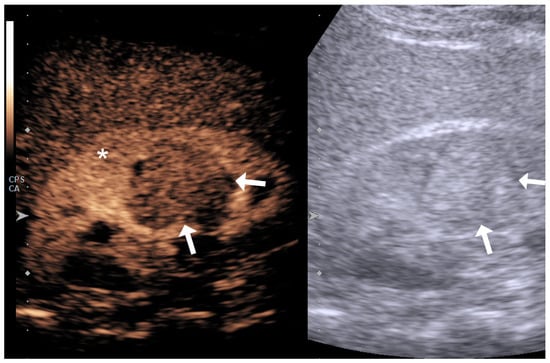

2.2. Image Acquisition and Analysis

4.1. Qualitative Evaluation